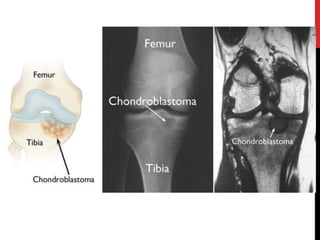

CHONDROBLASTOMA

It is rare type of benign tumor.

Genatic /signaling problem

It is appear in epiphysis usually in proximal humrus, femur or tibia.

Presenting with aching & tenderness adjacent joint. Fluid buildup

and affect motion

most chondroblastomas are small, well-marginated lesions, a small

subset of chondroblastomas behave in a much more aggressive

fashion. Some nonetheless become very large or have the capability

of metastasizing to the lungs and soft tissues.

TREATMENT

It requires surgery by scraping out and filling of

the cavity with bone grafting .